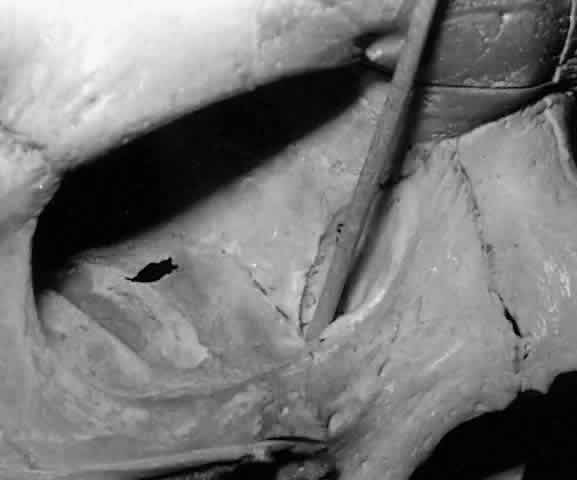

The parenchyma of the gland is made up of small lobules separated by a fine connective tissue network. The lacrimal gland has approximately 12 secretory ducts (Fig. 7), which average 0.66 mm in diameter and 2.31 mm in length.4 Two to five of them originate from the orbital lobe and six to eight from the palpebral lobe. The ductules from the orbital portion of the lacrimal gland pass through the parenchyma of the palpebral lobe before exiting into the superotemporal portion of the conjunctival fornix 4 or 5 mm above the upper border of the tarsus. One or two may open near the lateral canthus.5 Excision of the palpebral lobe may therefore interrupt drainage from the orbital lobe as well.

Fig. 7. Secretory ducts (arrow 1) of the right lacrimal gland (arrow 2) are seen passing to the palpebral conjunctiva (arrow 3). (Courtesy of James Sanderson, MD, Orkan Stasior, MD, and George Stasior, MD)

Sanderson and Stasior4 found islands of “peripheral” lacrimal glandular tissue below the lateral canthus unassociated with the main gland in 60% of cadaver specimens (Fig. 8). These peripheral islands of glandular tissue were found less commonly in or above the lateral canthal tendon.

Fig. 8. “Peripheral” lacrimal gland lobules (arrow 1) are seen below the right lateral canthus (arrow 2) and separate from the palpebral lobe of the lacrimal gland (arrow 3). (Courtesy of James Sanderson, MD, Orkan Stasior, MD, and George Stasior, MD)